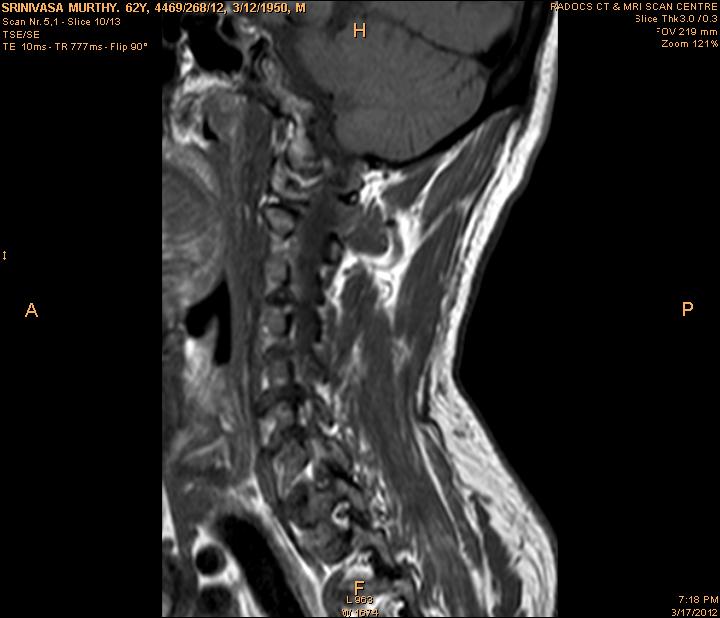

The proposed algorithm uses HSV color space to enhance spinal cord images since this color space offers many advantages such as color separation from intensity, reduced color distortion and efficient enhancement. The algorithm proposed takes advantage of this color space by performing enhancment operation on the intensity or value component and preserving the color information. The first column of Fig. 3 shows the original spinal cord test images followed by the extraction of value component presented in second column. Next, the third column of Fig. 3 shows the value component enhanced using the proposed multirate multiscale retinex algorithm. The modified version of the retinex algorithm presented here is capable of producing high quality reconstructed pictures, far better than the other researchers method.